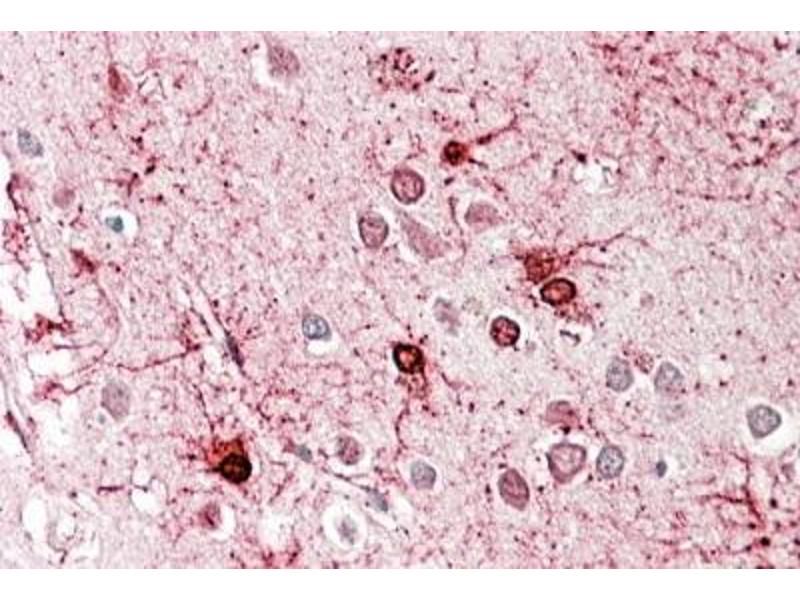

Immunohistochemistry: In paraffin embedded Human Cerebral Cortex shows mitochondrial staining in neuronal cell bodies and axons. Recommended concentration: 3-5 μg/mL.